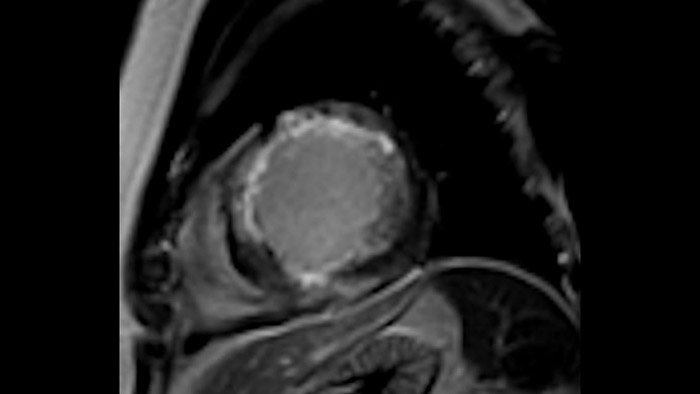

La diagnostica tradizionale non offre la visibilità necessaria per vedere gli effetti di un trattamento cardiaco o individuare disfunzioni prima che si verifichino i sintomi. Combinando la sequenza di acquisizione MRI Fast-SENC di Philips con lo strumento di analisi MyoStrain di Myocardial Solutions, i lievi cambiamenti precoci nella funzione cardiaca possono essere misurati direttamente.

La diagnostica odierna spesso non è in grado di rilevare le disfunzioni cardiache fino a quando non si manifestano sintomi. MyoStrain valuta la deformazione del miocardio in 48 segmenti cardiaci e fornisce ai medici uno strumento diagnostico utile per identificare con anticipo la disfunzione funzionale prima che il cuore nel suo complesso sia compromesso.